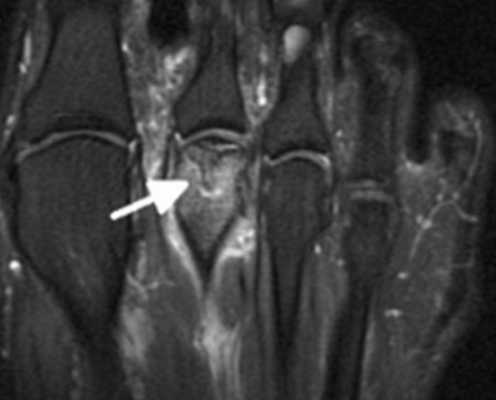

Болезнь Келлера, или болезнь Фрайберга, - аваскулярный некроз и перелом головок 2,3,4 плюсневых костей. Данное заболевание, распространённое главным образом среди женщин в возрасте 13-18 лет, чаще всего поражает головку 2-й плюсневой кости, особенно её тыльную поверхность. Часто встречается у лиц с длинной 2-й плюсневой костью (стопа Мортона). Патофизиология заболевания связана с постоянной микротравматизацией из-за перегрузки и последующим остеонекрозом из-за нарушения кровоснабжения.

Классификация аваскулярного некроза головок плюсневых костей.

Субхондральный перелом, виден только на МРТ

Коллапс тыльной суставной поверхности

Коллапс всей тыльной части головки, подошвенная часть интактна

Коллапс всей головки, сужение суставной щели

Прогрессирование деформирующего артроза, облитерация суставной щели

Для диагностики используется рентгенография и МРТ (см. картинки в классификации)